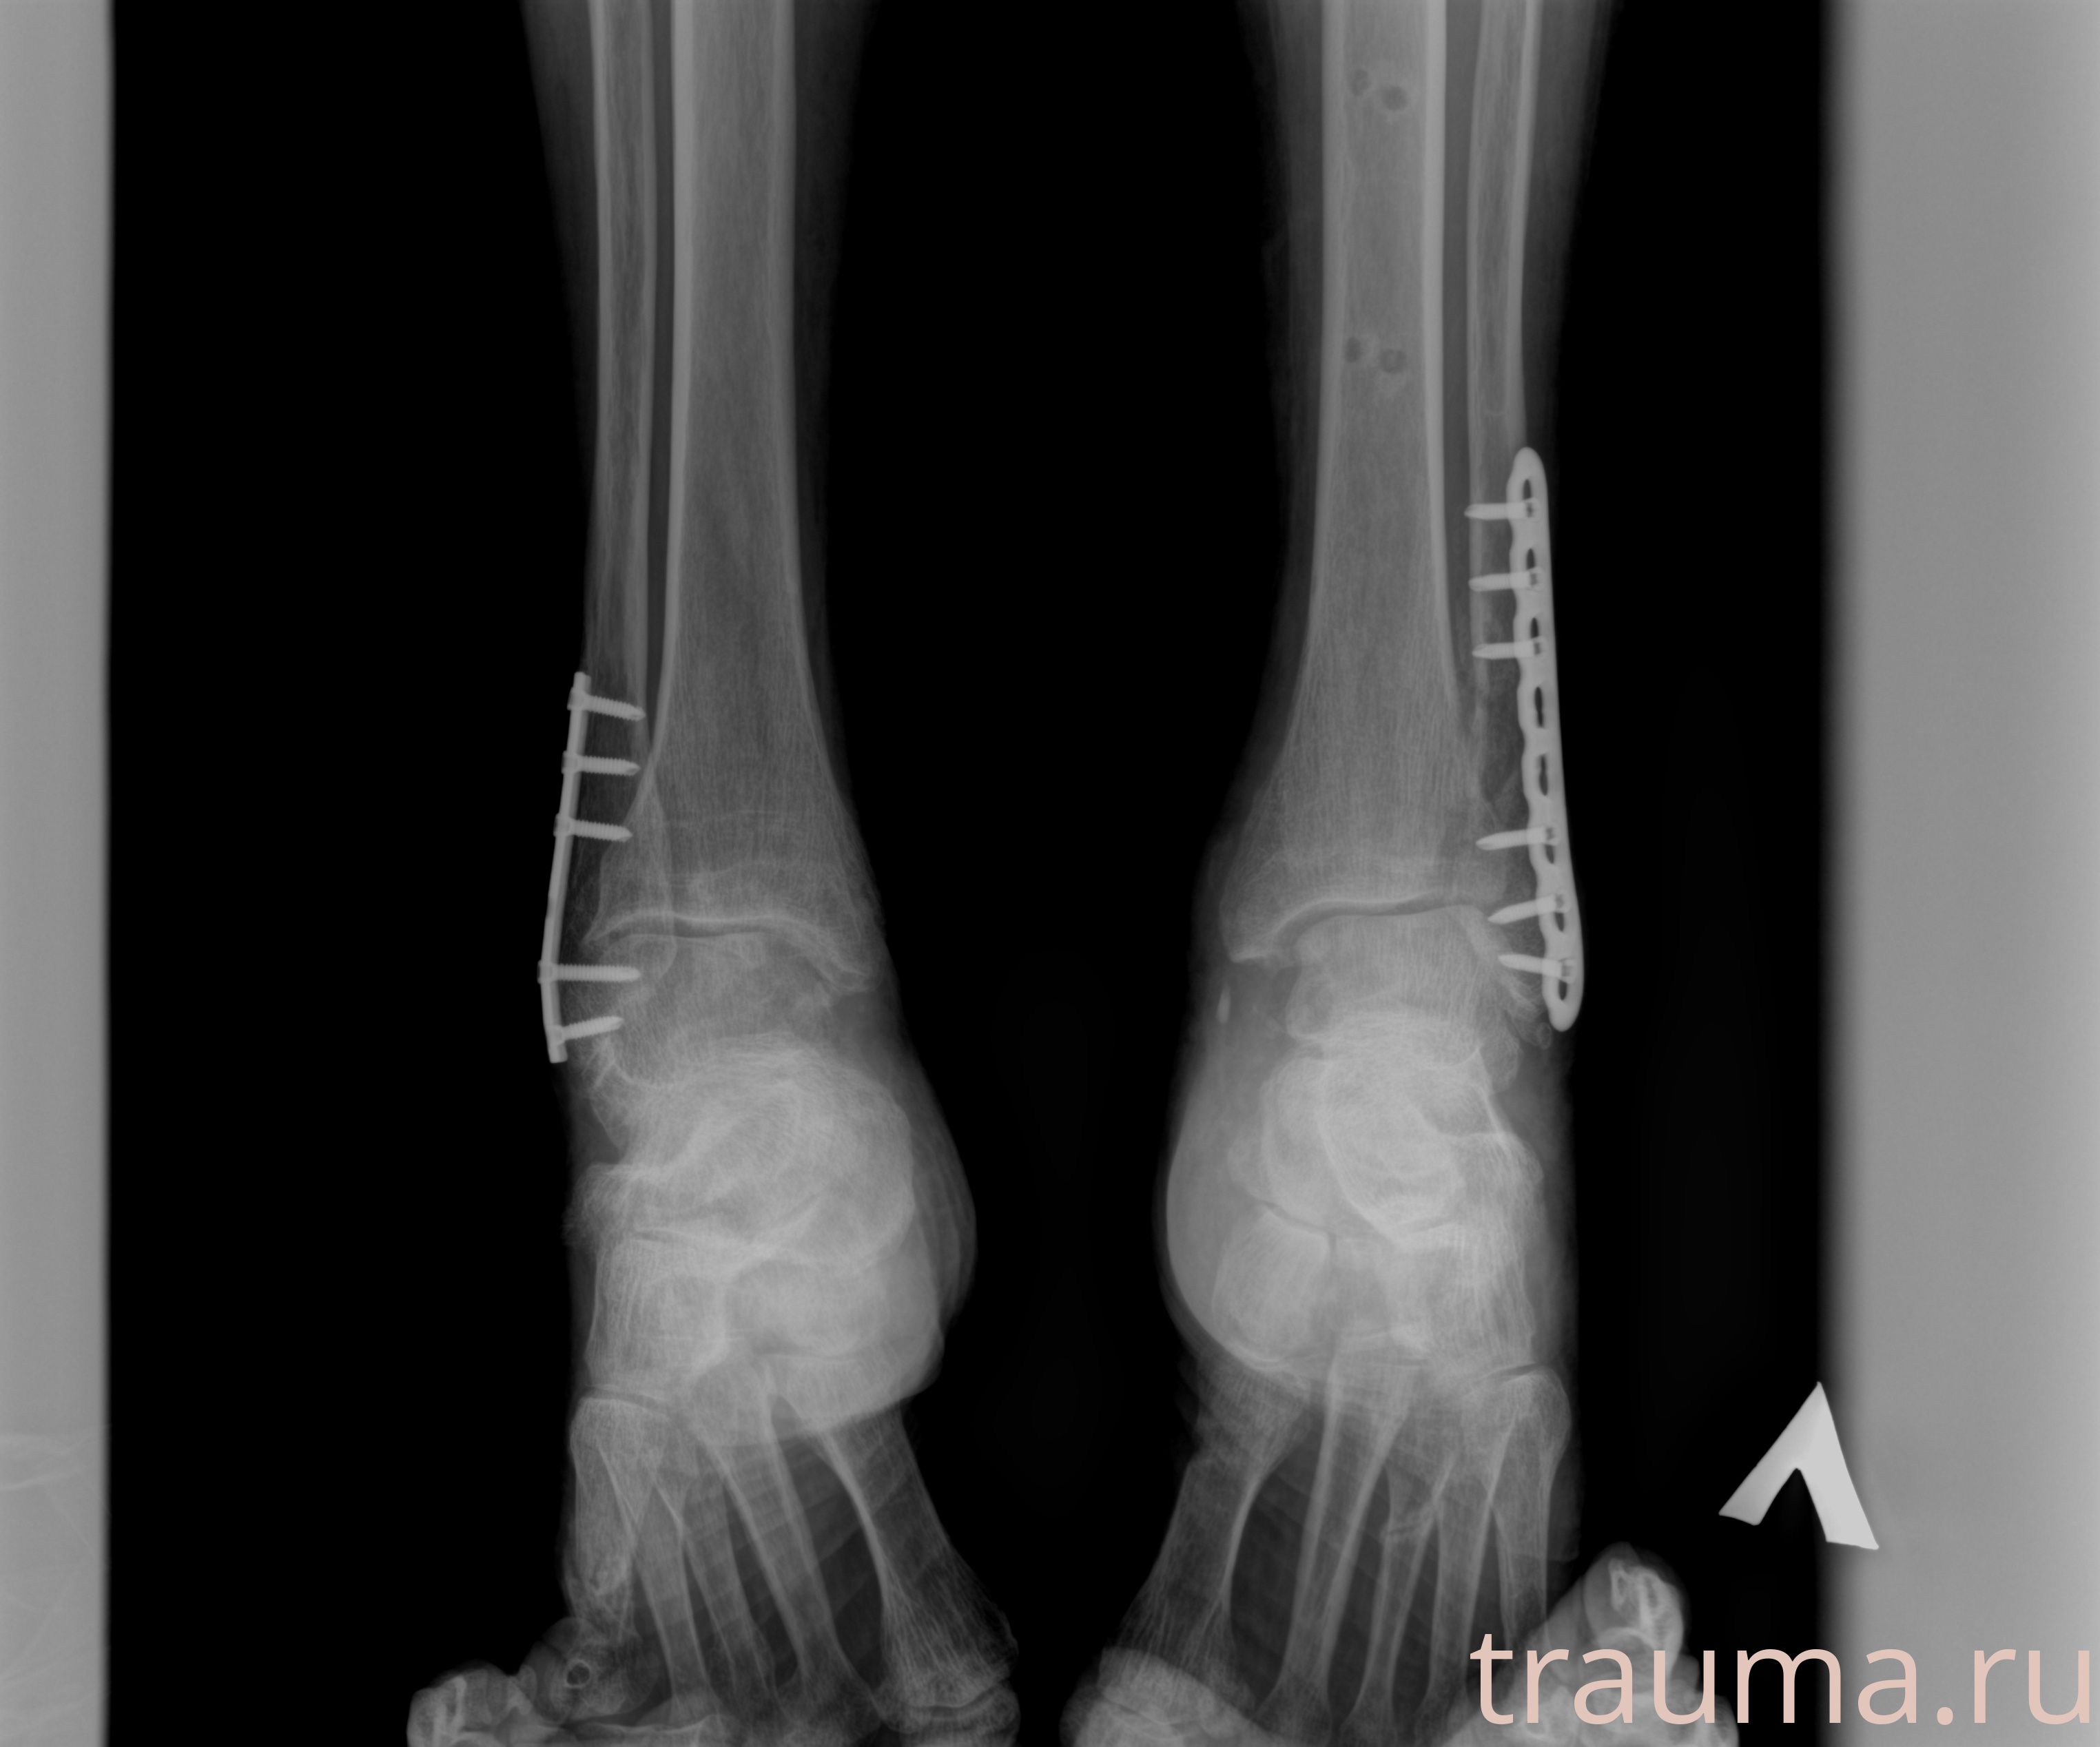

Рентгенограммы